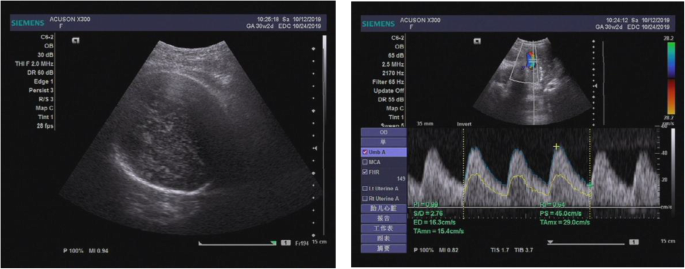

The abnormality was judged as consistent with a macrocystic congenital cystic adenomatoid malformation of the lung situated in the left lower thoracic cavity, and this abnormality led to a significant shift of the mediastinal structures to the right side. Repeated ultrasound scans during pregnancy showed that the malformation grew (Figs. 2, 3).

After birth, the patient showed shortness of breath and progressive aggravation to respiratory failure. Oxygen given through a hood could not correct the hypoxemia of the infant. Four hours after birth, the infant underwent endotracheal intubation and ventilator-assisted breathing. The CT scan showed that the cyst had caused severe compression of the heart, lungs, and mediastinum (Fig. 4). The symptoms could not be controlled with ventilator-assisted breathing or other treatments, and dyspnoea became worse on the 4th day after birth. A left lower lung thoracoscopic lobectomy was suggested, and consent was obtained from the parents.